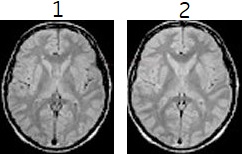

| 1 | Tailored RF On |

| 2 | Tailored RF Off |